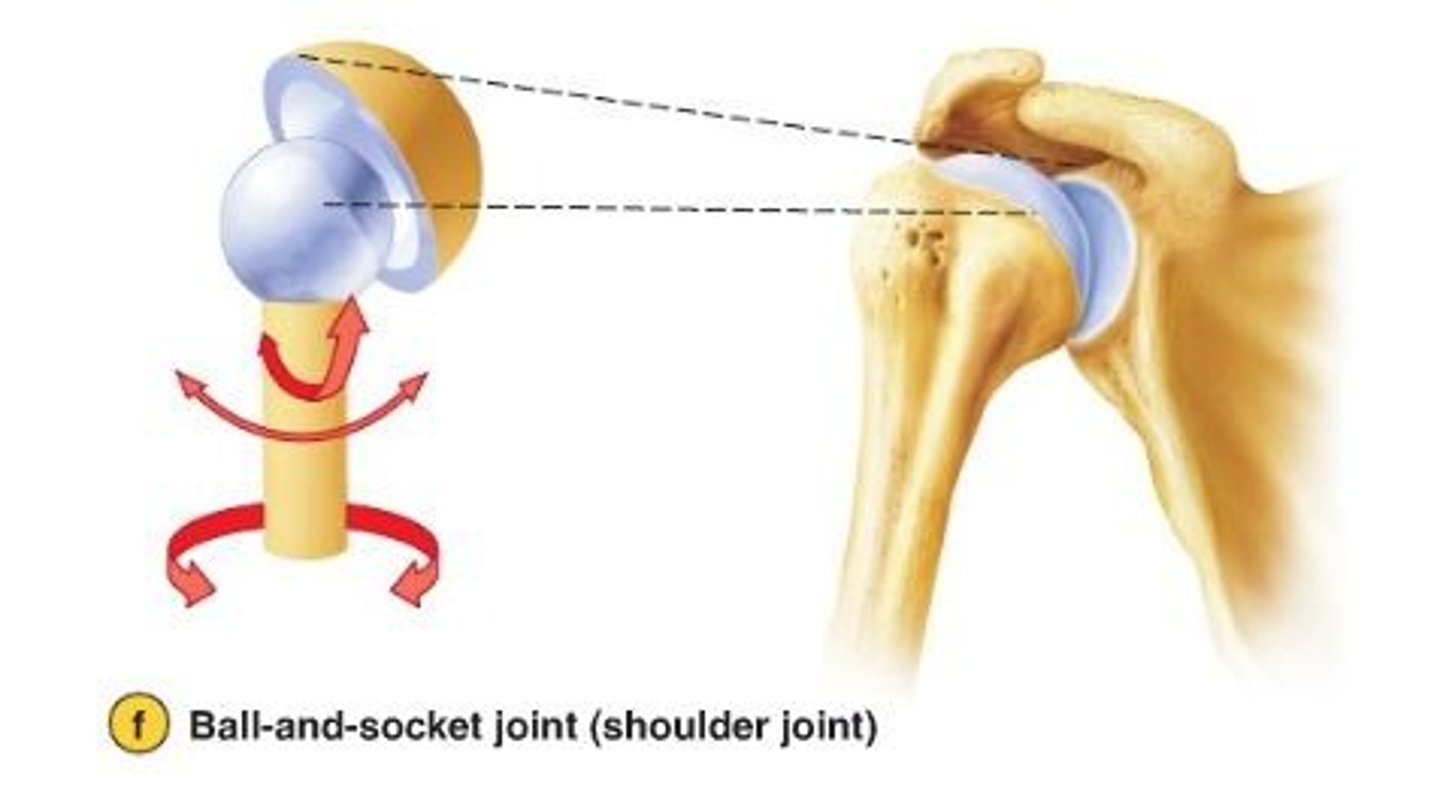

Ball and socket synovial joint

allow movement around multiple axes

-permits extension, flexion, abduction, adduction, circumduction, and rotation

ex: hip joint

A ball and socket joint has what type of movement

multiaxial